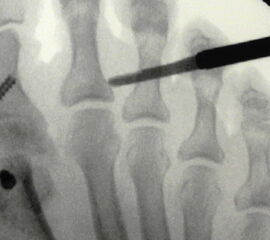

Der Fräsvorgang erfolgt mit niedriger Drehzahl von plantar nach dorsal. Die Osteotomie kann komplett oder subtotal erfolgen. Dabei sollte unbedingt beachtet werden, dass der Drehpunkt für die Fräse  generell der Bereich der Mini-Inzision ist (Abb 8). Eine zarte dorsale Knochenbrücke kann dabei im Sinne einer Keilosteotomie belassen werden. Nach Entfernen der Fräse erfolgt das Redressement nach plantar mit Korrektur der Dorsalextensionsfehlstellung und Verschluss des plantaren Keils. Alternativ kann die Grundgliedosteotomie auch von plantar über einen transtendinösen Zugang durchgeführt werden.

Bei einer rigiden Hammerzehendeformität ist zusätzlich zur Grundgliedosteotomie zumeist eine zusätzliche Osteotomie im Bereich des plantarflektierten Mittelgliedes zur vollständigen Korrektur nötig. Diese dorsalisierende Mittelgliedosteotomie kann ebenfalls als komplette oder als Keilosteotomie unter Erhalt einer plantaren Knochenbrücke durchgeführt werden. Diese erfolgt analog der für die Grundgliedosteotomie beschriebenen Technik:

Über eine unter Bildwandlerkontrolle auf Höhe der proximalen Mittelgliedanteile durchgeführte dorsomediale oder dorsolaterale Miniinzision wird mit der geraden schmalen Raspel die Strecksehne nach dorsal abgehoben um einen dem Knochen direkt anliegenden Kanal für die Fräse zu schaffen.  Unter erneuter Bildwandlerkontrolle der korrekten Lage der Fräse – proximal metadiaphysär, 90°-Winkel zur Längsachse des Mittelgliedes und nicht zu weit eingebracht und damit auf der Gegenseite perforationsgefährdend - erfolgt im Anschluss die komplette oder subtotale Osteotomie. Nach Entfernung der Fräse schließt sich das Redressment  mit Vervollständigung der Korrektur an.